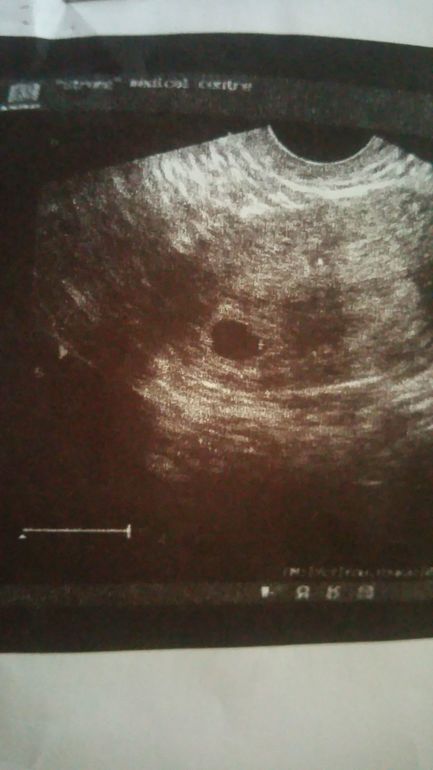

ВОТ ОНА МОЯ БУСИНКА !!!

Я еле себя держала чтоб не заплакать.Моя врач еще стояла рядом,и такая :Ой какая красота!Нам в день УЗИ 4 недели и 3 дня! Мы уже 10мм!Тонуса нет,угрозы тоже чему я очень рада!Так переживала что болит живот.Гиня говорит,может тонус был,но ношпа сняла спазм. Либо может кишки мои бушуют. (Я сейчас так думаю,потому что я вспомнила что не ходила в туалет два дня сорри))Я теперь наверное каждый пух и чих буду сюда выкладывать!:D

Через недельки 2 снова на УЗИ, на контроль сердцебиения. И воть)